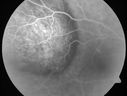

Choroidal Metastases - Both Eyes - Exudative Retinal Detachmentvu 1412 fois58-year-old man smoke a pack of cigarettes a day. He has had some ribcage pain for about the last two weeks. He also had a sinus infection for about two weeks, and he has also had hazy vision on the superior visual field in the left eye for about the last two weeks. vision is 20/25 in both eyes

Choroidal Metastases - Both Eyes - Exudative Retinal Detachmentvu 907 fois58-year-old man smoke a pack of cigarettes a day. He has had some ribcage pain for about the last two weeks. He also had a sinus infection for about two weeks, and he has also had hazy vision on the superior visual field in the left eye for about the last two weeks. vision is 20/25 in both eyes

Choroidal Metastases - Both Eyes - Exudative Retinal Detachmentvu 823 fois58-year-old man smoke a pack of cigarettes a day. He has had some ribcage pain for about the last two weeks. He also had a sinus infection for about two weeks, and he has also had hazy vision on the superior visual field in the left eye for about the last two weeks. vision is 20/25 in both eyes

Choroidal Metastases - Both Eyes - Exudative Retinal Detachmentvu 796 fois58-year-old man smoke a pack of cigarettes a day. He has had some ribcage pain for about the last two weeks. He also had a sinus infection for about two weeks, and he has also had hazy vision on the superior visual field in the left eye for about the last two weeks. vision is 20/25 in both eyes